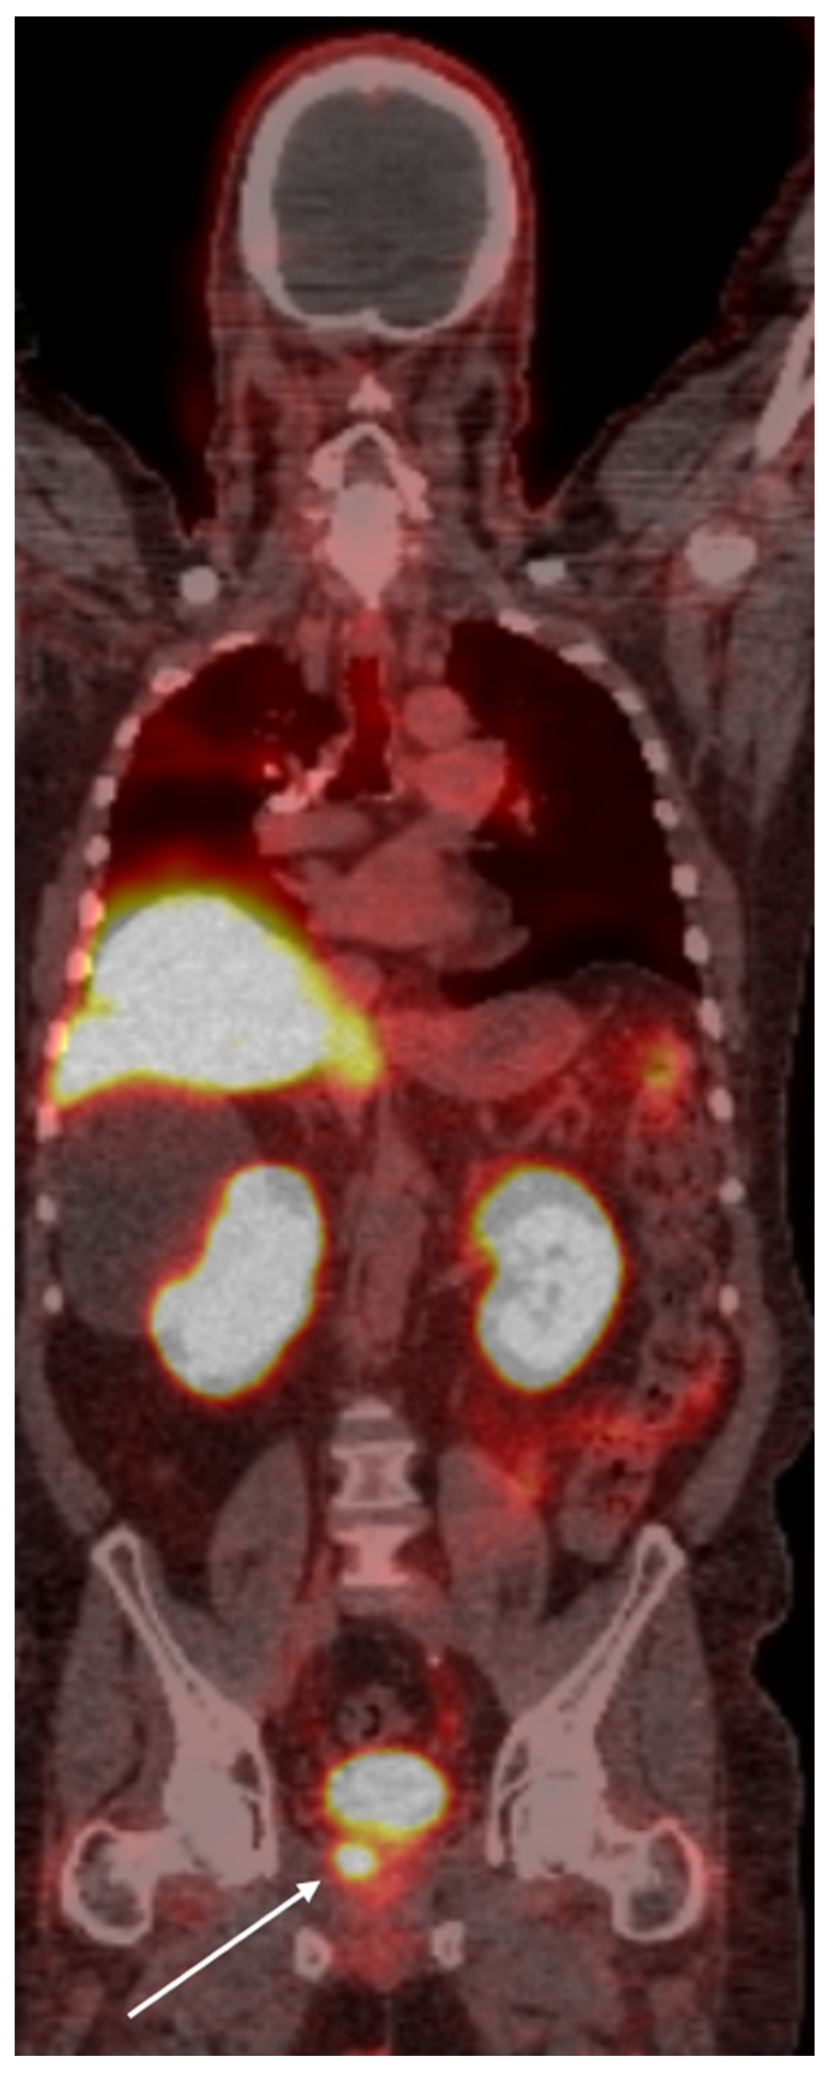

4. PSMA PET Imaging